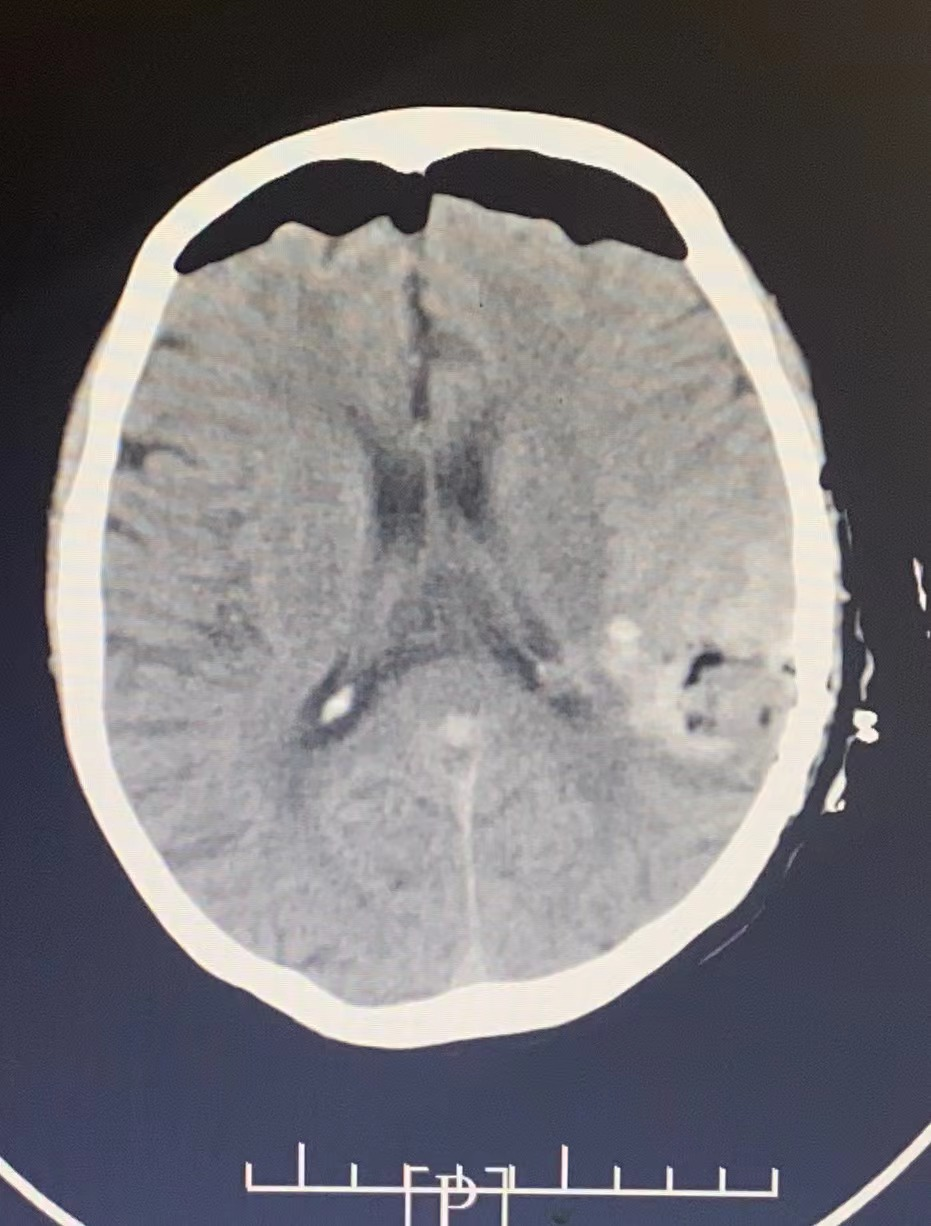

患者行神經(jīng)內(nèi)鏡下腦出血清除術,術后瞳孔等大等圓,對光反應存在。術后第1天患者即可刺痛睜眼、握手。

圖片

手術后